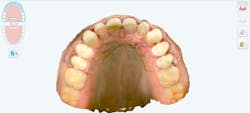

The new digital approach (figures 2–13) to an osseous crown lengthening procedure involves photographs, radiographs, intraoral scans, and CBCT data for a facially driven treatment plan. This approach starts with the end result in mind and ultimately requires fewer appointments for the patient. It also leads to more predictable esthetic results.

Prior to treatment, the patient mentioned he had previously undergone orthodontic treatment. After analyzing all intraoral iTero scans and an occlusogram to account for restorative functionality, the patient was found to have a class 1 sagittal relationship, adequate arch length within the transverse plane, and normal 33% overbite across the vertical plane. His occlusal relationships in each dimension were verified to be functional and healthy, meaning that no additional alignment adjustments were necessary.

Utilizing a facially driven treatment plan, the facial photographs were merged with the CBCT scan to assess bone levels, and the central incisors were digitally planned to exhibit a new length of 11.5 mm, to enhance the patient’s long facial structure. The new width of the veneers could then be generated to be 85% of this measurement to achieve the golden proportion for optimal esthetics. Once the surgical guide is designed in Exocad to achieve these coronal margins, the guide design is exported to SprintRay to be printed with a snug fit for accurate coronal margination for the final restorations later on.

New scans of the patient’s mouth were taken eight weeks after the osseous surgery, prior to the minimal veneer preparations. The original digital plan then can be evaluated, which typically involves minor changes. The next phase design would be printed in the office following sharing the STL files (stereolithography). This allows the office to create a restorative matrix and reduction guide for the dentist. Careful preparation was utilized so as to stay within enamel only, which many studies have shown allows for more predictable bonding and longevity of veneer restorations. Standard tissue retraction methods were used, and the preps were scanned with iTero 5D Plus. The provisionals created from the digital plan would allow the patient to test-drive the new smile prior to the final 10 porcelain restorations being placed. The patient was seen a few days after his preps to allow any modifications before the final 10 e.max pressable veneers were created.